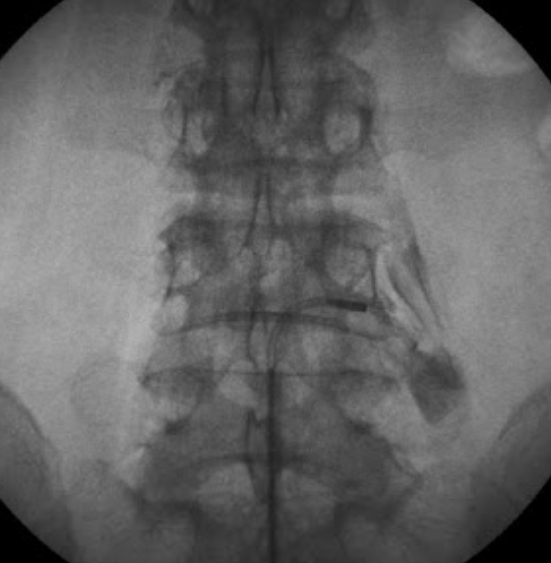

경피적 신경성형술은 흔히 척추 시술이라고 많이 불리고 있으며, 개인병원에서 많이 시행하고 있습니다. 꼬리뼈를 통해 척추의 경막외강에 약 1~2mm 정도의 카테터를 삽입하여 시행합니다. 카테터를 영상 장비하에 실시간으로 모니터를 확인하면서 추간판 탈출이 있는 위치로 이동을 시키고 디스크 주변으로 염증을 제거하는 약물인 스테로이드를 뿌려주어 통증을 감소시키는 시술입니다. 약물을 탈출된 디스크에 직접 주입하여 염증을 빠르게 제거할 수 있다는 장점으로 통증을 효과적으로 감소시킬 수 있습니다. 하지만 탈출된 디스크를 직접 제거할 수 없기 때문에 디스크의 신경 압박에 의한 통증은 호전시킬 수 없습니다.